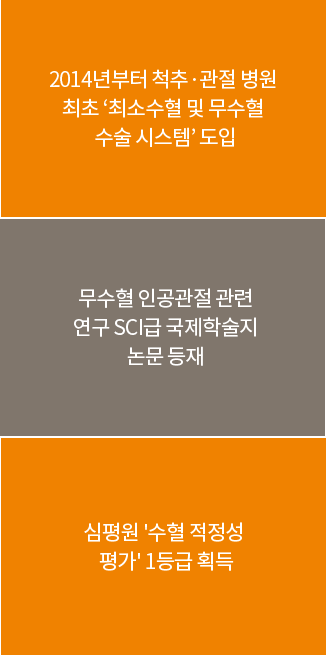

바른세상병원의

무수혈 · 양측동시 인공관절수술

# 무수혈 인공관절수술이 가능한 이유

의료진의 빠른 판단과 기술력으로 절개 부위를 줄이는 최소 침습

무수혈을 위한 수술시스템 표준화

수술 중 양극 전기소작을 이용한 충분한 지혈로 출혈 최소화

수술 후 첨단 조혈제와 철분제로 환자의 혈액 생산량 증대

# 무수혈 인공관절수술의 장점

자기 혈액의 산소 운반 능력이 유지돼 부작용이 줄고 면역력과 체력 유지

출혈을 최소화하기 위해 최소절개를 하여 수술 후 빠른 회복

입원기간이 줄어들어 경제적 부담 감소

수혈로 인한 감염 위험 없음